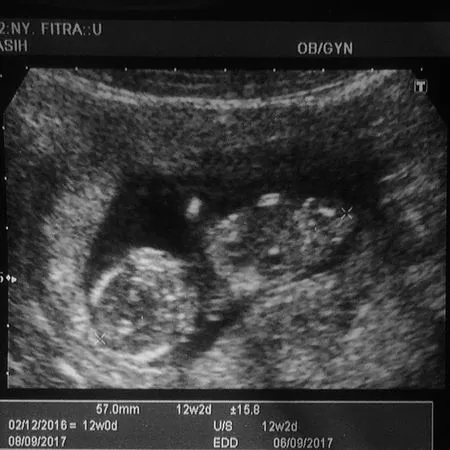

Usg Bayi Dalam Kandungan Usia Kehamilan 13 14 Minggu Janinnya Sehat Bikin Gemas Youtube